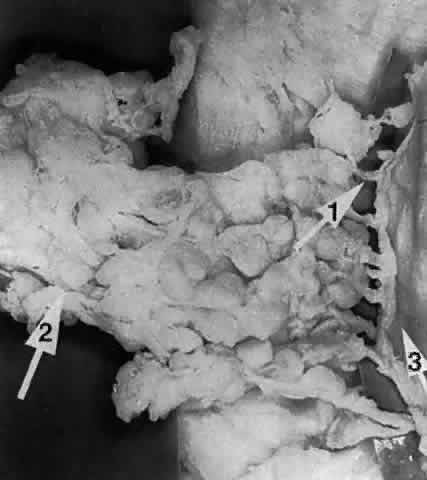

The parenchyma of the gland is made up of small lobules separated by a fine connective tissue network. The lacrimal gland has approximately 12 secretory ducts (Fig. 7), which average 0.66 mm in diameter and 2.31 mm in length.4 Two to five of them originate from the orbital lobe and six to eight from the palpebral lobe. The ductules from the orbital portion of the lacrimal gland pass through the parenchyma of the palpebral lobe before exiting into the superotemporal portion of the conjunctival fornix 4 or 5 mm above the upper border of the tarsus. One or two may open near the lateral canthus.5 Excision of the palpebral lobe may therefore interrupt drainage from the orbital lobe as well.

Fig. 7. Secretory ducts (arrow 1) of the right lacrimal gland (arrow 2) are seen passing to the palpebral conjunctiva (arrow 3). (Courtesy of James Sanderson, MD, Orkan Stasior, MD, and George Stasior, MD)

Sanderson and Stasior4 found islands of “peripheral” lacrimal glandular tissue below the lateral canthus unassociated with the main gland in 60% of cadaver specimens (Fig. 8). These peripheral islands of glandular tissue were found less commonly in or above the lateral canthal tendon.

Fig. 8. “Peripheral” lacrimal gland lobules (arrow 1) are seen below the right lateral canthus (arrow 2) and separate from the palpebral lobe of the lacrimal gland (arrow 3). (Courtesy of James Sanderson, MD, Orkan Stasior, MD, and George Stasior, MD)